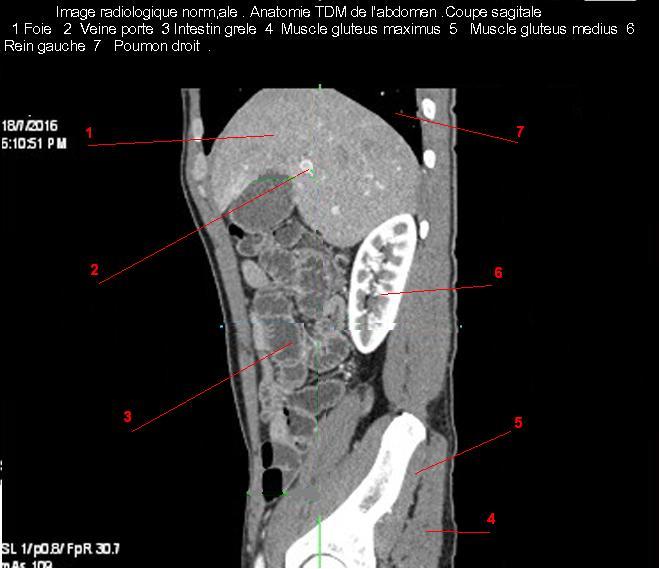

Image TDM

normale du foie :

Image TDM du foie en coupe sagitale a travers

branche droit de la veine portale , la

vesicule biliaire et le rein droit . Double de click pour agrandir . |